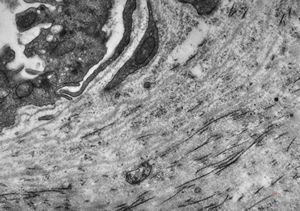

F, 39y. | collagenous and elastin fibers from corium

F, 39y. | collagenous and elastin fibers from corium

F,68y. | collagenous and elastin fibers from corium